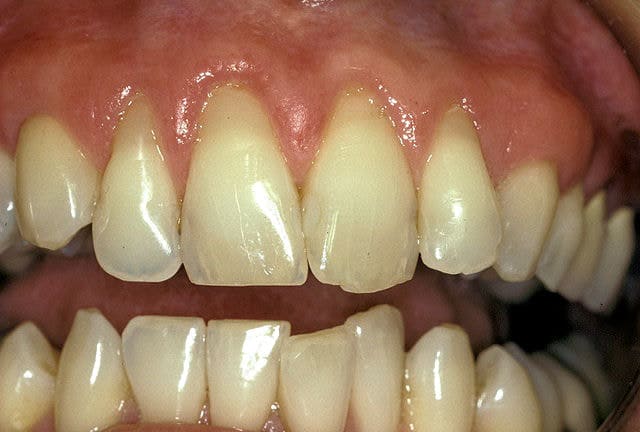

Before

Patient: Jill